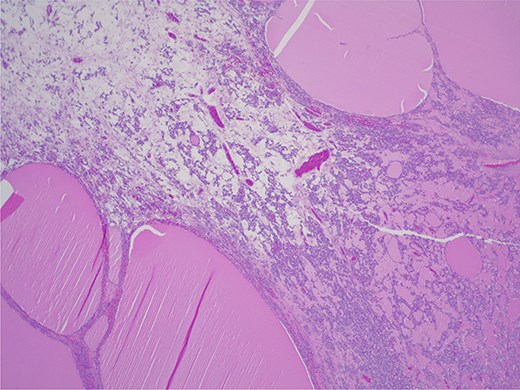

Final histopathological examination confirmed the diagnosis of struma ovarii. On gross examination, the tumor was composed predominantly of thyroid tissue and contained a cyst filled with sebaceous material and hair (Fig. 3). The cut surface of the ovarian mass was partly solid and partly cystic, with a gelatinous, pale-yellow, goiter-like appearance (Fig. 4). Microscopically, the lesion demonstrated thyroid follicles of varying sizes filled with colloid (Figs 5 and 6), with no evidence of malignant transformation. The patient recovered well and has remained asymptomatic under regular follow-up. At 3 years post-surgery, she shows no evidence of disease.

Struma ovarii—thyroid tissue is the dominant component with large and small colloid-containing follicles: H&E ×25.